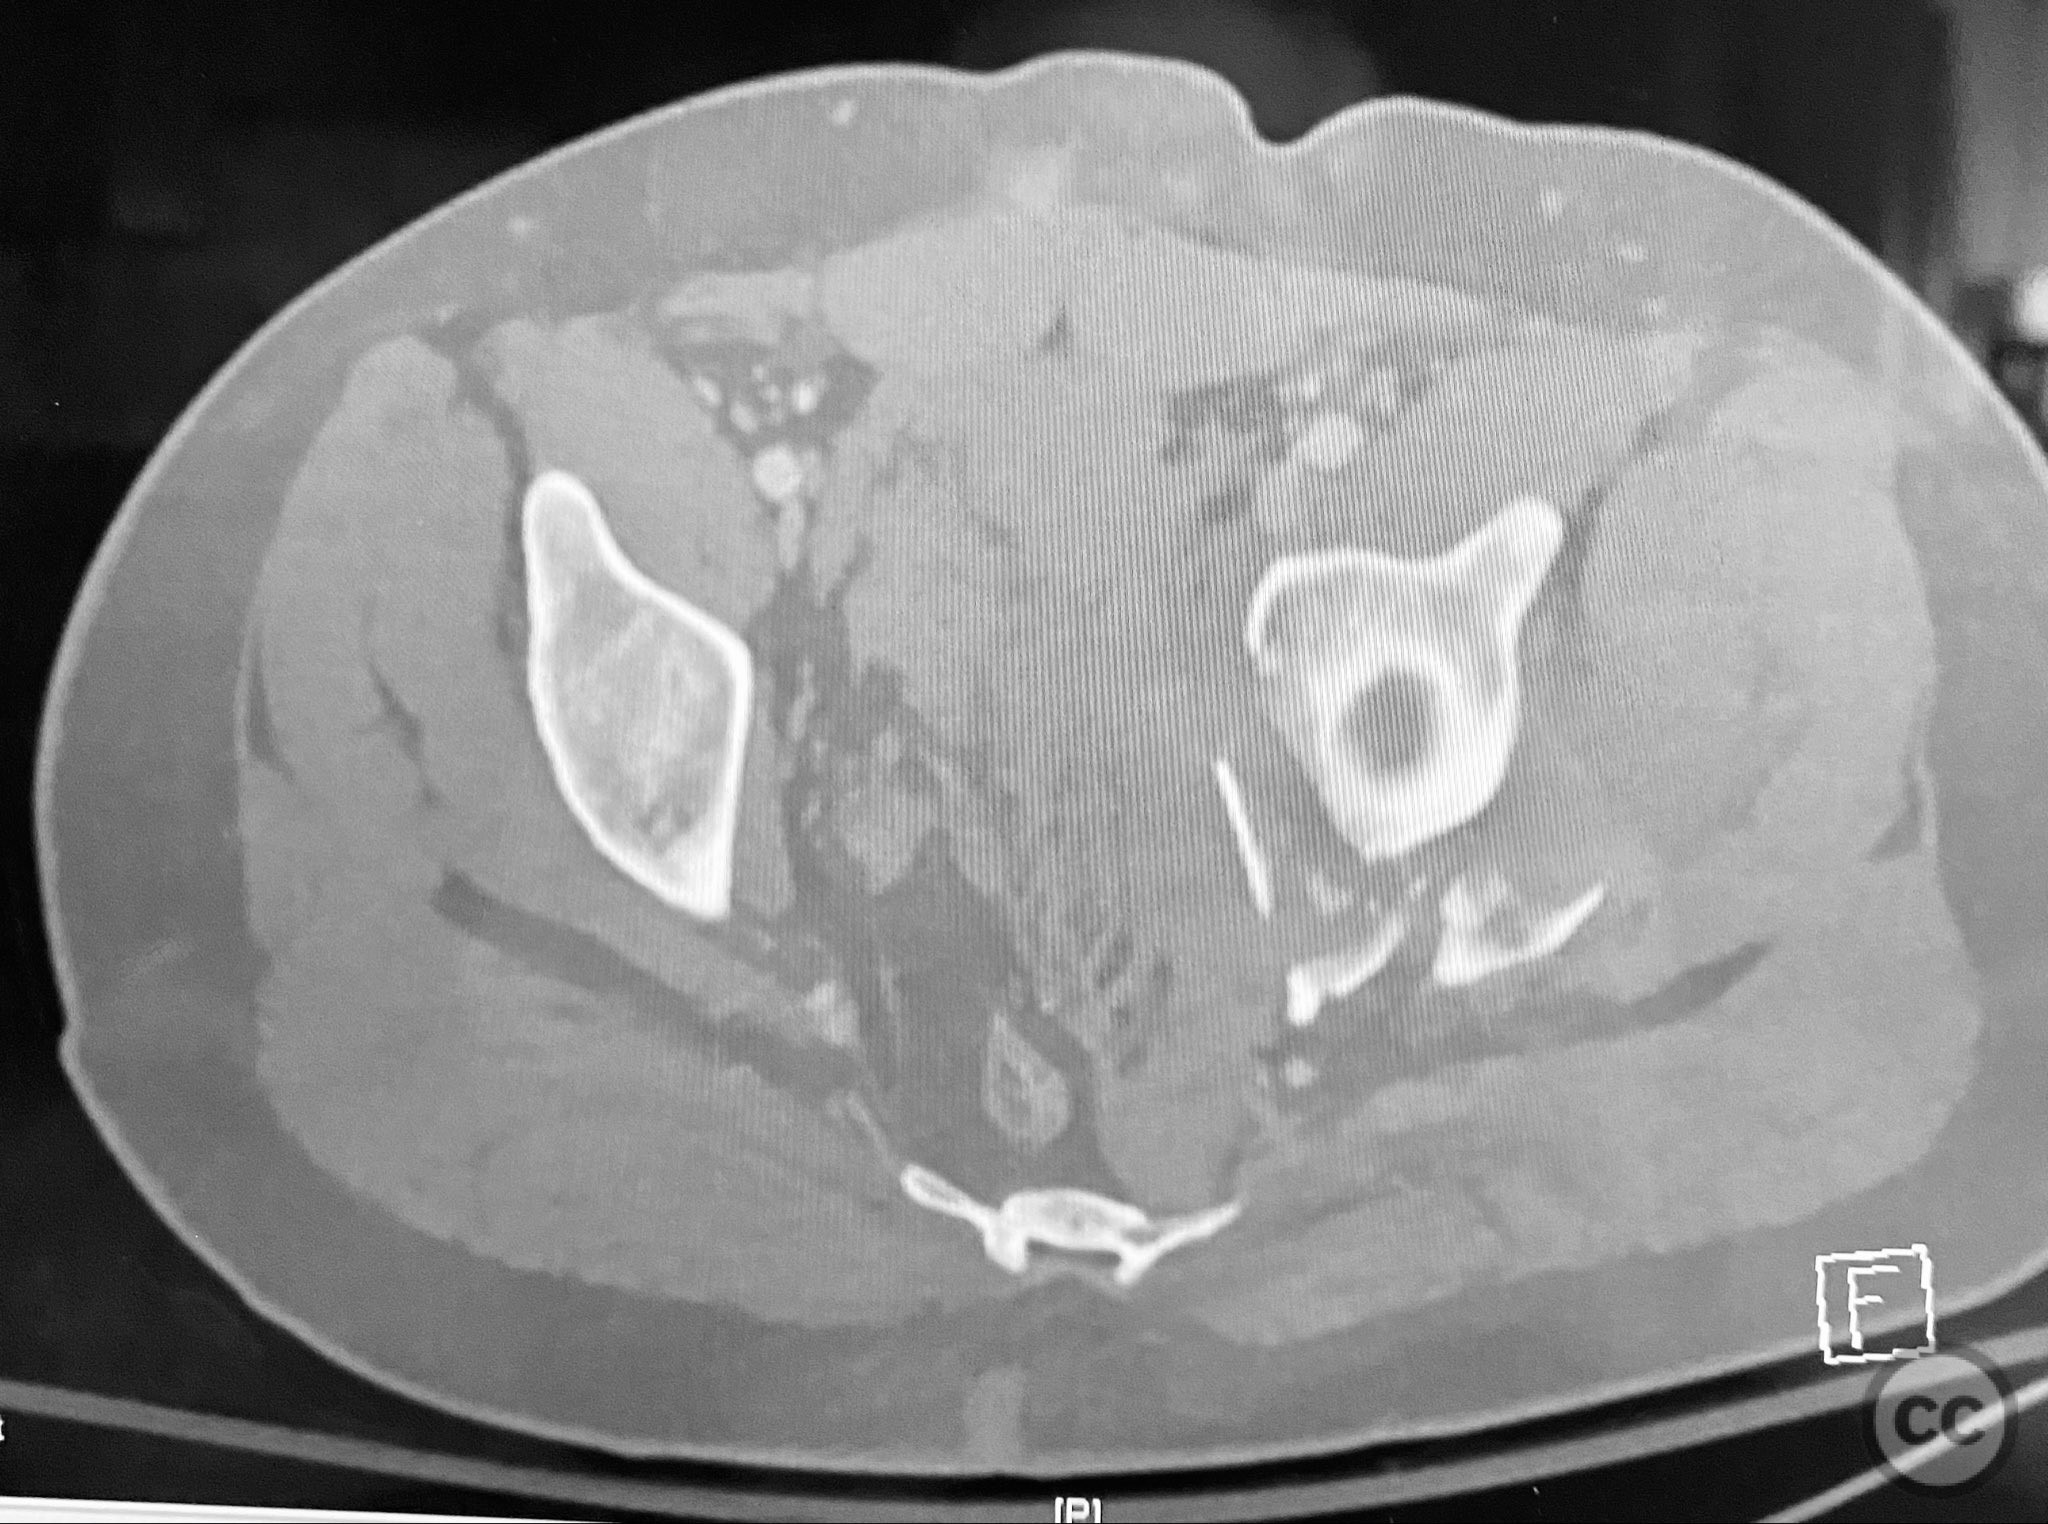

Clinical and radiological findings:  A patient presented with a displaced associated both column acetabular fracture, characterized radiographically by the presence of the "spur sign" on the anteroposterior (AP) pelvis film, indicating the caudal aspect of the intact ilium exposed by medial displacement of the articular fragments. The spur was more clearly visualized on the obturator oblique rendered image. Axial computed tomography (CT) images demonstrated the intact ilium, medially displaced anterior column (AC) and posterior column (PC) fragments, and provided detailed visualization of surrounding soft tissues, including vascular structures enhanced by contrast. Multiplanar CT reconstructions (axial, sagittal, coronal) and 3D renderings were utilized for comprehensive fracture and soft tissue assessment. The patient’s overall clinical condition was a significant factor in surgical planning.

The operative sequence was dictated by the patient’s overall clinical status, necessitating staged management. Intraoperative attention was paid to implant placement during AC fixation to preserve access for subsequent percutaneous PC fixation. Postoperative CT confirmed satisfactory reduction and fixation of both columns, with appropriate implant positioning and no evidence of neurovascular compromise or significant soft tissue complications.